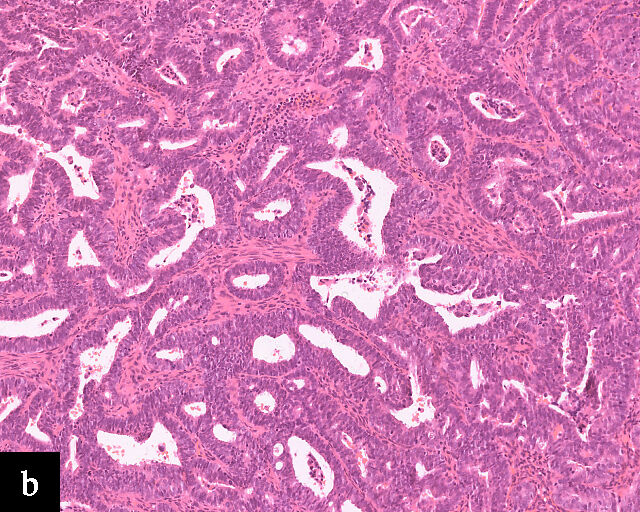

4

Gastric-type adenocarcinoma on cervical cytology.

In terms of epidemiology, HPV-associated precancerous lesions and HPV-associated cervical carcinomas are preventable by HPV vaccination,51 and decreases in incidence and mortality related to cervical carcinomas have been observed in regions in which effective population-level HPV vaccination has been adopted.52 As a result, the incidence of HPV-independent carcinomas is gaining increased clinical significance.53 Because these carcinomas are relatively uncommon and morphologically diverse, encompassing multiple morphologically distinct subtypes of adenocarcinomas with a wide variation in degree of differentiation,53 diagnosis by cervical cytology is challenging54 (Figure 4). Even so, cytomorphological assessment may allow the detection of HPV-independent cervical carcinomas, particularly morphologically high-grade tumors such as HPV-independent squamous cell carcinomas and clear cell adenocarcinomas.55 On the other hand, the absence of detectable precursor lesions on cytologic specimens, the subtle or non-HPV-related cytologic features of these tumors, and potential false reassurance from negative HPV testing can make HPV-independent adenocarcinomas more difficult to recognize microscopically. Consequently, the false-negative rate for cervical cytology in HPV-independent adenocarcinomas may be higher than that in HPV-associated adenocarcinomas.56